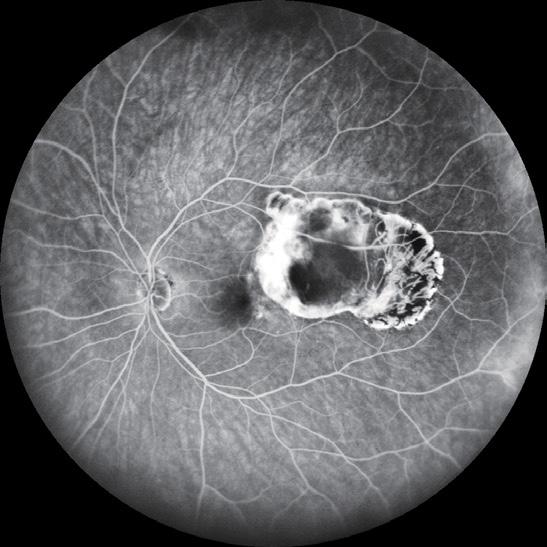

Post-paediatric cataract surgery Glaucoma: A: 3.5 years old child with cataract surgery done in infancy. Glaucoma with enlarged corneal diameter and a dislocated IOL are seen. One previous Ahmed glaucoma valve (AGV) in supero-temporal quadrant has failed to control IOP adequately; B: A second AGV plate is sutured in the infero-temporal quadrant. A closed chamber vertical translocation of haptics to glued IOL is then done sitting temporally, taking advantage of smaller vertical diameter of cornea; C: Adequate length of the externalised haptics of the IOL is seen; D: Haptics are tucked in. A well-centred IOL is seen. The AGV tube tip is positioned posterior to the iris in front of the IOL. Adequate vitrectomy is performed during IOL translocation as well as after inserting the tube tip